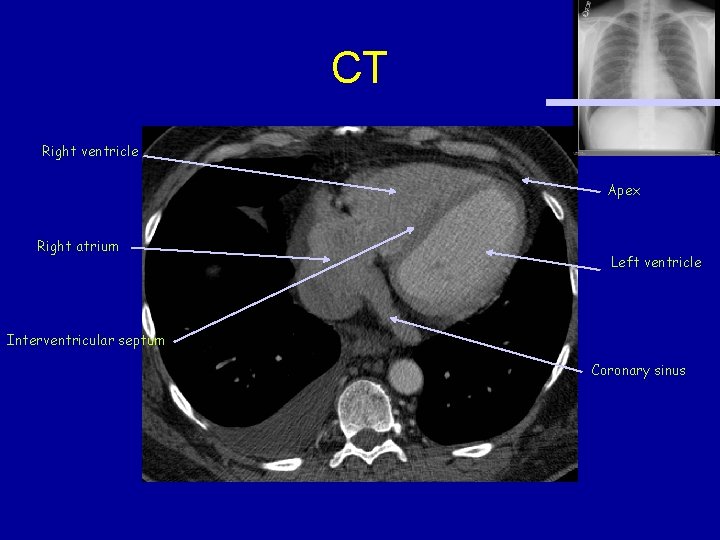

CT Right ventricle Apex Right atrium Left ventricle Interventricular septum Coronary sinus